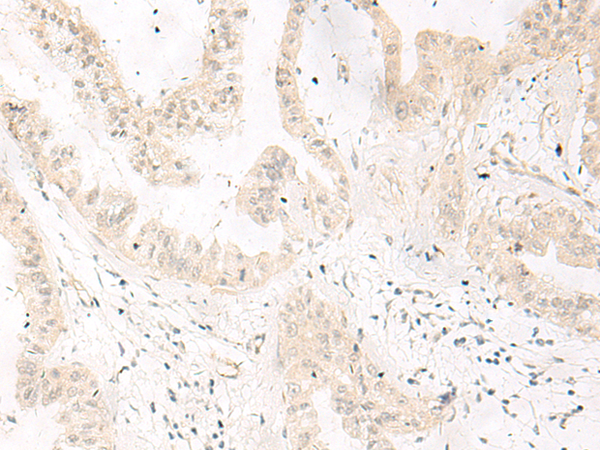

IHC positive control: |

Human liver cancer |

IHC Recommend dilution: |

10-50 |